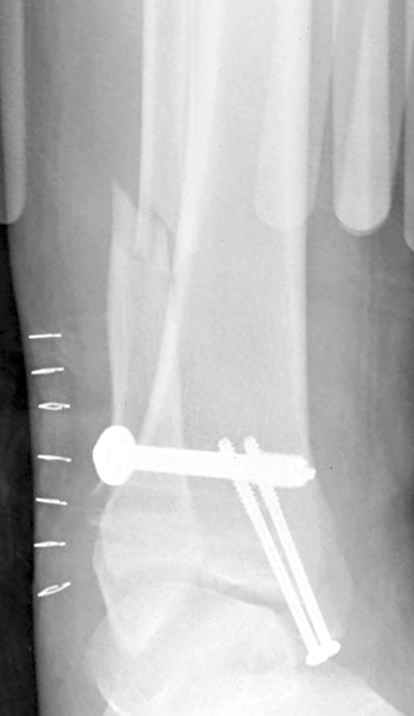

15 ноября прямой

|

15 ноября боковой

15 ноября трехчетвертной

12 января прямой

12 января боковой

12 января трехчетвертной

Вариант с артродезом уже обсудили. Хотя, после увиденых снимков, пессимизм насчет восстановительной операции у меня, например, несколько уменьшился. Особенного уж какого-то остеопороза не видно даже на январских снимках. Можно черед мини-доступы убрать винты, аппаратом вправить малоберцовую кость, устранить подвывих стопы. Ну а дальше фиксировать малоберцовую пластиной сзади. А может, и напряженной Y-спицей попробовать - Анатолий Федорович, как Вы полагаете? Внутреннюю - то, что осталось, если уже не получится сделать спицами и проволокой, то что-то типа пластики дельтовидной связки. А может, и не трогать ее вовсе... В общем, выбор непростой,

Если до сих ничего не сделано, с артродезом сустава в данный момент я бы повременил, на выставленных январских снимках хорошо сохранившийся сустав, а в "мортиз" (трехчетвертной) и на боковых снимках не менее 5 мм укорочение малоберцовой кости. Косые переломы лучше фиксировать пластинами, как то мы разбирали случай, где было отмечено, что это закон "таранная кость всегда следует за малоберцовой".

тарнная кость находится в латеральном подвывихе, что снижает шансы этого сустава.

Это видно по снимку - середина суставной поверхности тарана должна быть против середины суставной поверхности тибии. Причины, что это не так:

1. Внутренняя лодыжка не на месте

2. наружная лодыжка укорочена

3. Возможно есть компрессионный перелом наружной части пилона тибии.

В подобных случаях лучше всего начинать с главной цели - вправить таран, временно зафиксировать спицами и используя таран как шаблон поставить на место лодыжки, неважно в какой последовательности.